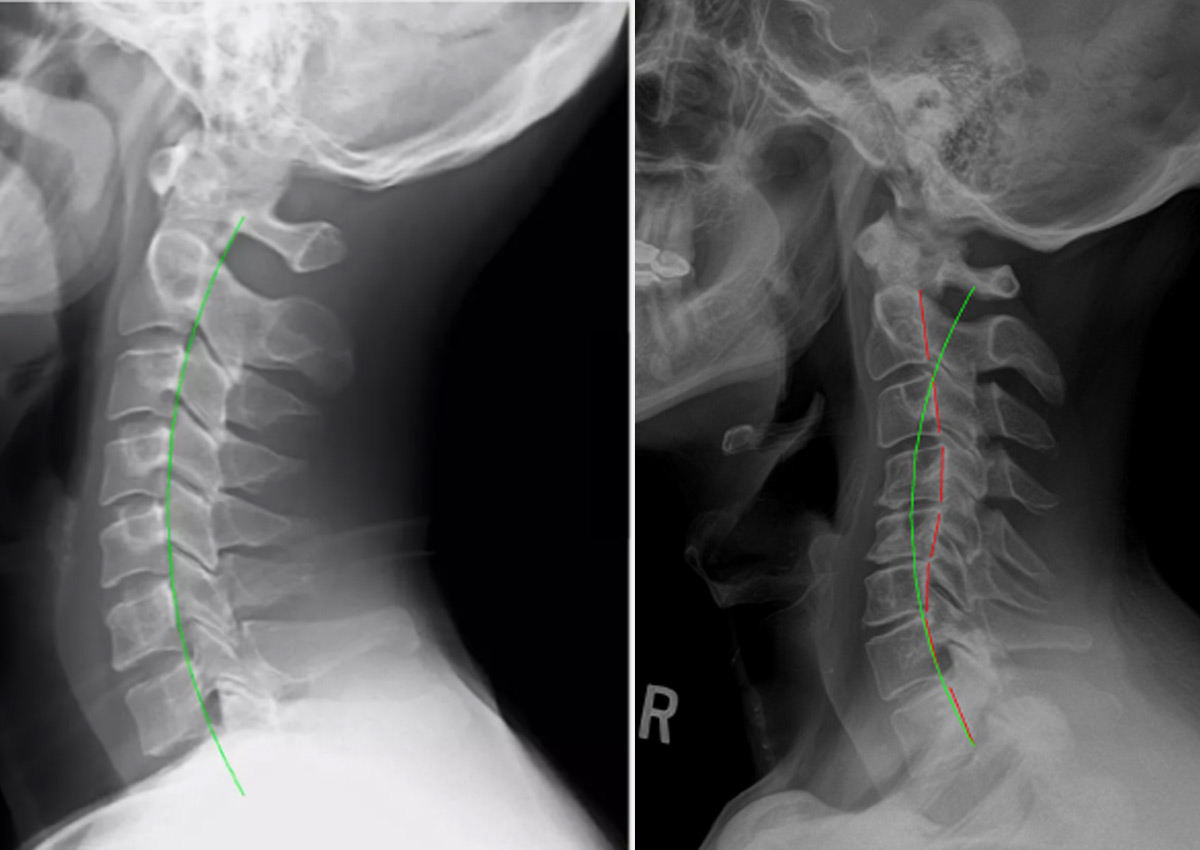

This trauma doesn't just cause acute pain; it frequently results in Structural Ligamentous Instability (SLI) and causes the cervical vertebrae to shift out of alignment. If left untreated, whiplash creates scar tissue, chronic stiffness, severe headaches, and long-term degeneration.

The immediate aftermath of an accident may involve symptoms like debilitating stiffness, upper back aching (linked to neck and shoulder pain ), or radiating numbness down the arms. What often complicates care is that these injuries—even from low-speed impacts may not show up on routine X-rays and can take days or weeks to fully manifest. Our approach immediately focuses on nerve integrity and spinal alignment. We gently and incrementally restore the natural curve of the neck, release pressure on the compressed nerves, and ensure the delicate connection between your spine and brain remains clear. We understand the specific patterns of injury caused by seatbelts and steering wheels, ensuring your entire back and pelvis (back pain and sciatica) are assessed for subluxations that often compound the initial whiplash injury.